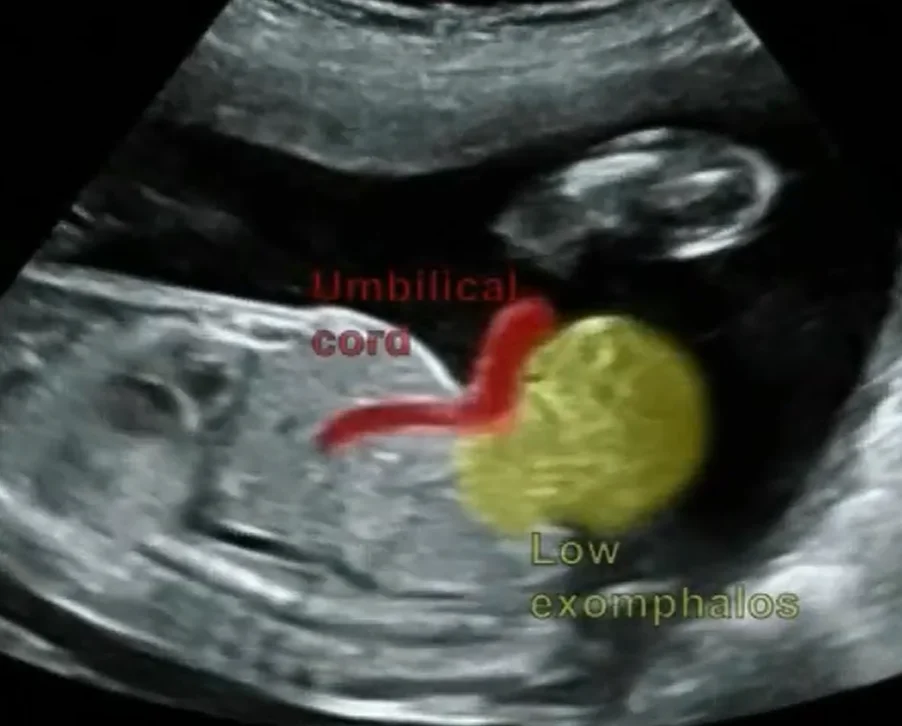

Thoát vị rốn thai nhi (Omphalocele)

• Thoát vị rốn thai nhi (Omphalocele)